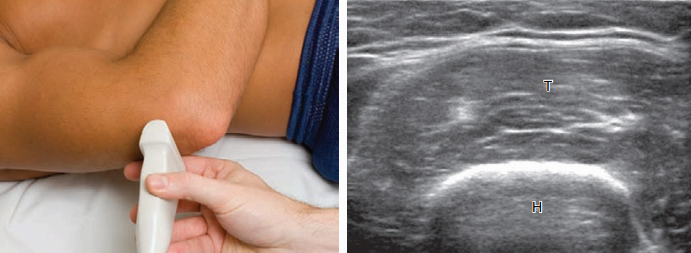

뒤쪽검사(posterior) 팔꿈치의 뒤쪽 구조물을 검사하려면 환자의 팔꿈치를 굽혀야 한다. 누운 자세에서 환자의 손을 배 위에 가로 방향으로 놓는다. 검사할 중요 구조물들은 뒤쪽관절오목, 위팔세갈래근, 팔꿈치머리 부위의 연조직(soft tissue)이다.

몸 쪽 팔꿈치 뒤쪽에서 탐촉자를 시상면으로 놓으면 위팔뼈가 높은 에코와 소리그림자의 특징적인 뼈 윤곽으로 보인다. 위팔뼈 몸통에서 팔꿈치관절 쪽으로 이동하면 팔꿈치오목이 뚜렷하게 보이며, 가로면 영상에서도 확인할 수 있다. 이 오목은 정상적으로 높은 에코의 뒤쪽 팔꿈치 지방덩이로 채워져 있으며 관절액과 관절내소체(intra-articular bodies)의 검사 또한 이 부위에서 시행한다. 높은 에코의 도더래와 작은 머리 유리연골도 확인할 수 있다. 팔꿈치오목의 표층에서는 낮은 에코의 위 팔세 갈래근이 보이고 아래쪽으로는 높은 에코의 힘줄이 팔꿈치돌기에 부착되는 것을 볼 수 있다. 팔꿈치를 펴면 팔꿈치돌기의 표층 연조직 부위에서 팔꿈치윤활주머니 액을 검사할 수 있다. 팔꿈치윤활주머니 액을 검사할 때는 탐촉자를 두꺼운 겔(gel) 층 위에 압력에 의해 소량의 액이 눌려 보이지 않을 수 있기 때문이다. 앞서 언급한 구조물들을 검사할 때에는 시상면 영상이 가장 중요하지만 가로면 영상 또한 해부학적 구조물과 특징적인 병적 소견을 확인하는 데 있어 도움이 된다.